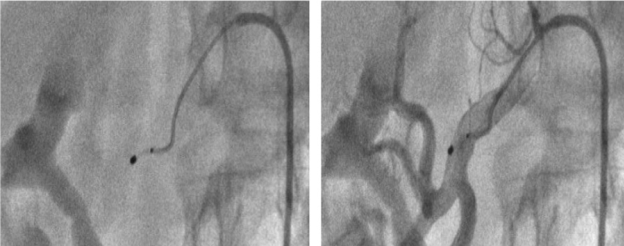

Hình 4 : Hình ảnh X quang của kỹ thuật triệt đốt thần kinh giao cảm động mạch thận trong các nghiên cứu Symplicity với ống thông đốt Symplicity®, Flex-Catheter, Medtronic/Ardian Inc. USA

Symplicity HTN-1 (catheter-based renal sympathetic denervation for resistant hypertension: a multicentre safety and proof-of-principle cohort study) là nghiên cứu đầu tiên về tính khả thi, tính an toàn và hiệu quả trên người của phương pháp triệt phá thần kinh giao cảm động mạch thận qua đường ống thông. Nghiên cứu được thực hiện trên nhiều trung tâm tại Australia, 45 bệnh nhân tăng huyết áp kháng trị đã được triệt đốt thần kinh giao cảm động mạch thận hai bên bằng năng lượng sóng tần số radio. Quy trình kỹ thuật trong Symplicity HTN-1: Các bệnh nhân sau khi thỏa mãn các tiêu chuẩn lựa chọn của nghiên cứu sẽ được chuẩn bị cho một thủ thuật thăm dò chảy máu và được chụp động mạch thận chọn lọc qua đường động mạch đùi. Sau đó, một ống thông dẫn (guide catheter) đường kính 8 French sẽ được luồn vào lỗ vào động mạch thận, qua đó, ống thông đốt với kích thước nhỏ hơn sẽ được đưa sâu vào trong động mạch thận để tiến hành triệt đốt thần kinh giao cảm từ phía nội mạch. Ống thông đốt với đặc điểm có thể điều khiển gấp duỗi được bởi bác sĩ thủ thuật (steerable) cho phép triệt đốt thành một đường xoắn ốc vòng quanh lòng động mạch thận từng bên. Cũng tương tự như quy trình triệt đốt các rối loạn nhịp tim bằng năng lượng tần số radio, quá trình đốt mạch thận được kiểm soát bởi các thông số nhiệt độ và điện trở nhằm đảm bảo năng lượng đủ để gây tổn thương mô, cắt đứt các đường dẫn truyền thần kinh giao cảm nhưng không tăng nhiệt độ quá cao gây tổn thương nội mạc làm hẹp động mạch thận. Trong Symplicity HTN-1, có 2 biến chứng liên quan đến thủ thuật được ghi nhận: 1 trường hợp lóc tách nội mạc mạch thận do đầu ống thông đốt. Động mạch thận bị lóc tách sau đó đã được đặt Stent; 1 trường hợp giả phình động mạch đùi do chọc mạch.

Ống thông đốt sử dụng trong các nghiên cứu Symplicity (Symplicity®, Flex-Catheter, Medtronic/Ardian Inc. USA) được thiết kế chuyên biệt cho triệt đốt trong lòng động mạch thận nhưng vẫn dựa trên nguyên lý sử dụng năng lượng tần số radio. Ngoài những ưu điểm vốn có vì được thiết kế chuyên biệt, nhược điểm của loại ống thông này là giá thành cao (xấp xỉ 7000 USD) nên khó có khả năng ứng dụng rộng rãi trên các bệnh nhân ở các nước thu nhập thấp trong đó có Việt Nam.